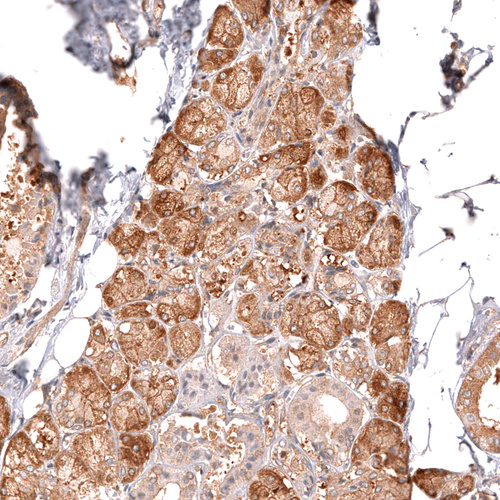

Immunohistochemical staining of human salivary gland shows strong cytoplasmic positivity in glandular cells.